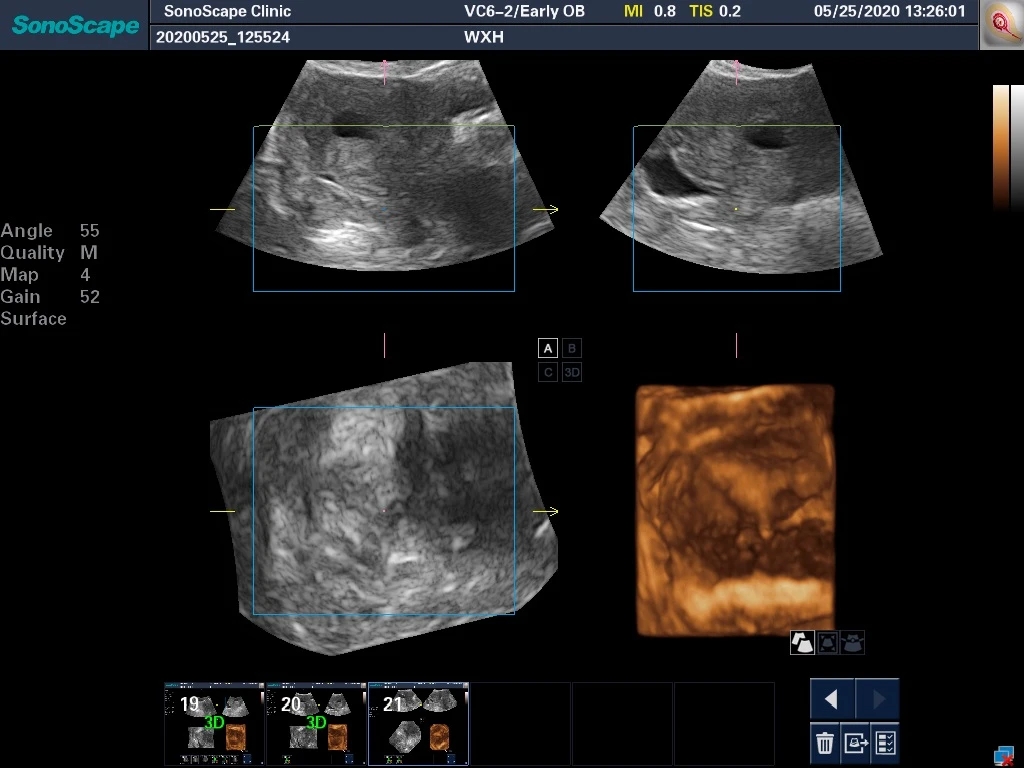

返回彩超,看看术后的情况。下图展示的是宫腔恢复后的容积,显然远远大于手术前两个小空间的面积。

这台彩超还允许我们在手术中直接进行3D重建成像。